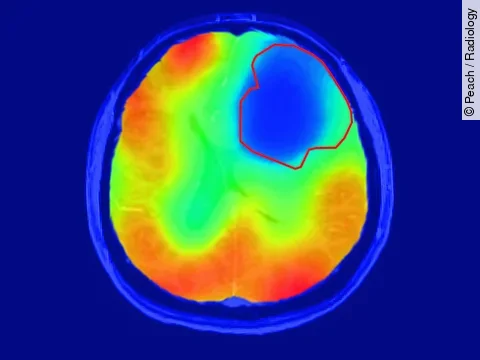

Am Deutschen Krebsforschungszentrum haben Wissenschaftler einen Weg gefunden, mithilfe von Sauerstoff im MRT Gehirntumoren besser zu diagnostizieren. Die Bildgebungstechnik markiert aggressive und niegriggradige Tumoren. Sie bedarf keiner radioaktiven Sauerstoffvariante.